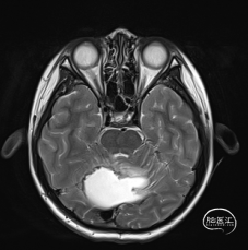

现病史:患者18个月前无明显诱因出现间断头痛,休息后可缓解,开始未予重视,未行特殊治疗。1周前患者无明显诱因出现恶心、呕吐,就诊于当地医院,行颅脑MRI提示:小脑囊实性占位性病变,首先考虑毛细胞星型细胞瘤。现患者为求进一步治疗就诊于我院,门诊以“脑肿瘤”收入院。患者自发病以来神志清,精神可,饮食睡眠正常,二便如常,体重未见明显下降。

术前MRI

术前诊断

小脑肿瘤(毛细胞型星形细胞瘤?)